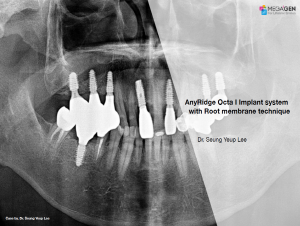

Miguel Stanley, Filipa Calheiros Braga, and Beatriz Mota Jordao, AnyRidge, Immediate Loading, Anterior Maxilla, Scientific background, single replacement